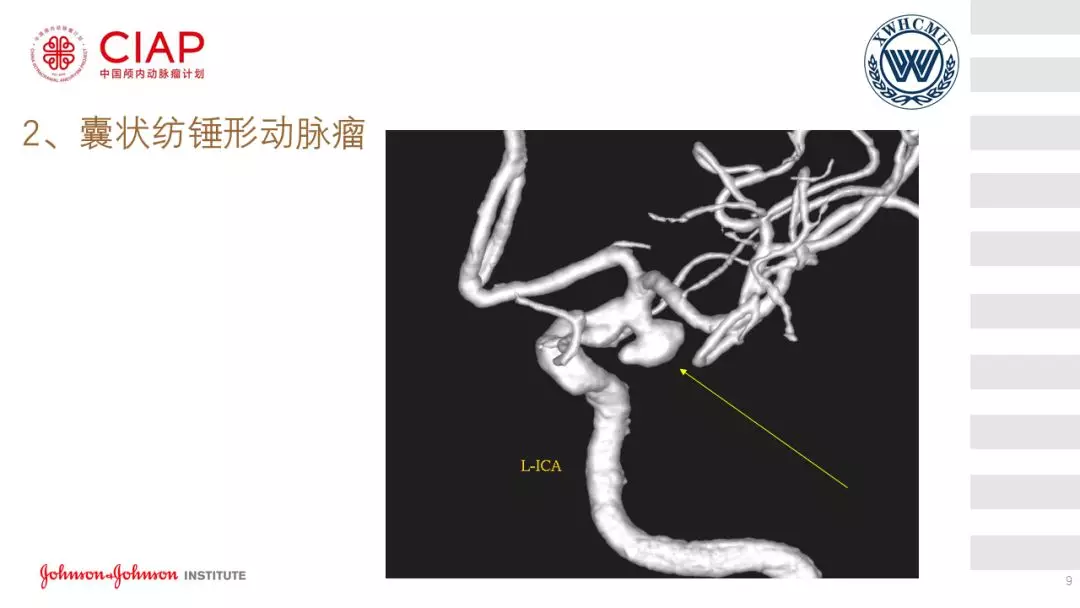

张鹏教授:不同辅助方法下栓塞动脉瘤弹簧圈的选择